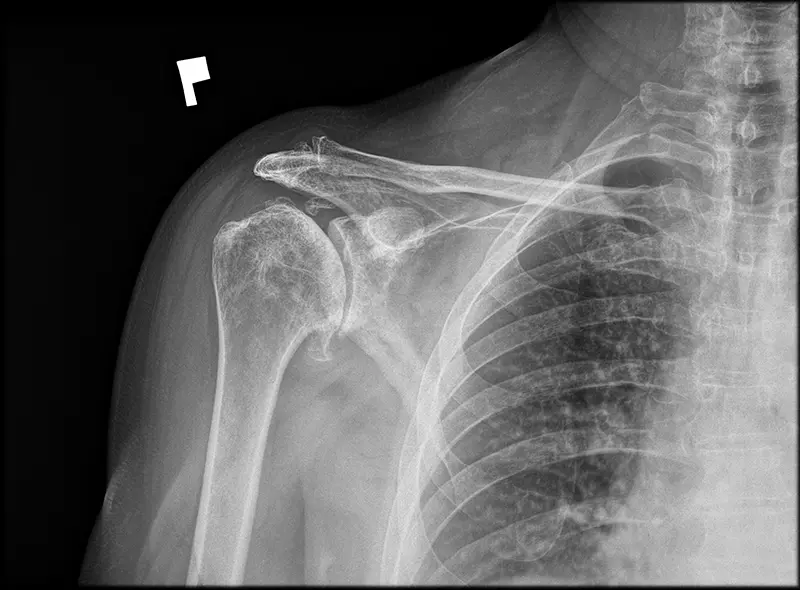

W przypadku braku znaczącej poprawy lub nasilania się objawów, warto rozważyć konsultację z chirurgiem. Przede wszystkim ma to na celu potwierdzenie, czy objawy są wynikiem choroby zwyrodnieniowej stawu barkowego. Po drugie, lekarz może ocenić, czy wskazane jest zastosowanie protezy stawu barkowego, jednocześnie wyjaśniając pacjentowi zasady, korzyści i ryzyko związane z taką procedurą.